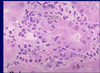

Acute pyelonephritis; neutrophil infiltration

Bacteria in Acute Pyelonephritis; look like pale blue smudges

Fungus (arrow) in Acute Pyelonephritis

WBC casts in the medulla in acute pyelonephritis